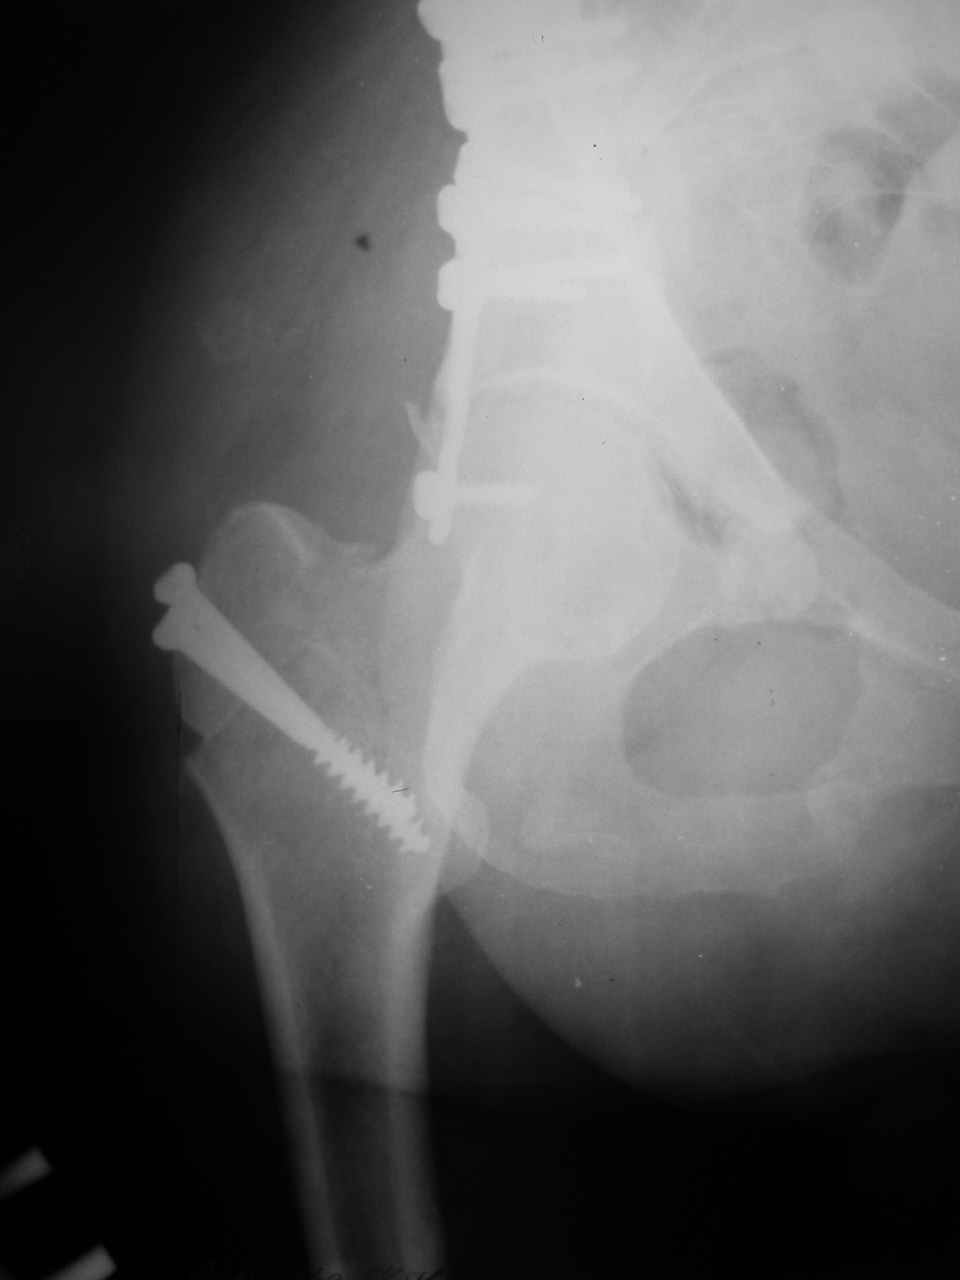

форуме и скелетном вытяжении. С репозицией и фиксацией задней колонны и отдельно задне-верхней стенки впадины проблем не возникло. Послеоп. Рг граммы в приложении. Если возникнут какие-либо дополнения или поправки - был бы признателен.

Спасибо за комментарии и рекомендации. Откровенно говоря, больного я прооперировал на прошлой неделе, через 5 дней после аварии и проблем с ним пока никаких нет, на удивление при достаточно обширной диссекции (илиофеморальный доступ) болей практически нет, так что больной самостоятельно садится в кровати, выполняет активные движения в оперированном суставе, сгибая до 60 градусов пока, далее с ассистенцией.

Причиной обращения к сообществу были возникшие непосредственно после операции сомнения и разочарования полученным качеством репозиции: а надо ли было трогать перелом вообще, репозиция передней колонны технически была очень сложна для меня, хотя реконструкции была в той же последовательности, что Д-р А.В.Рунков рекомендовал, в какой-то момент безуспешных манипуляций стал думать о *вторичной конгруэнтности*, которую не так давно обсуждали на